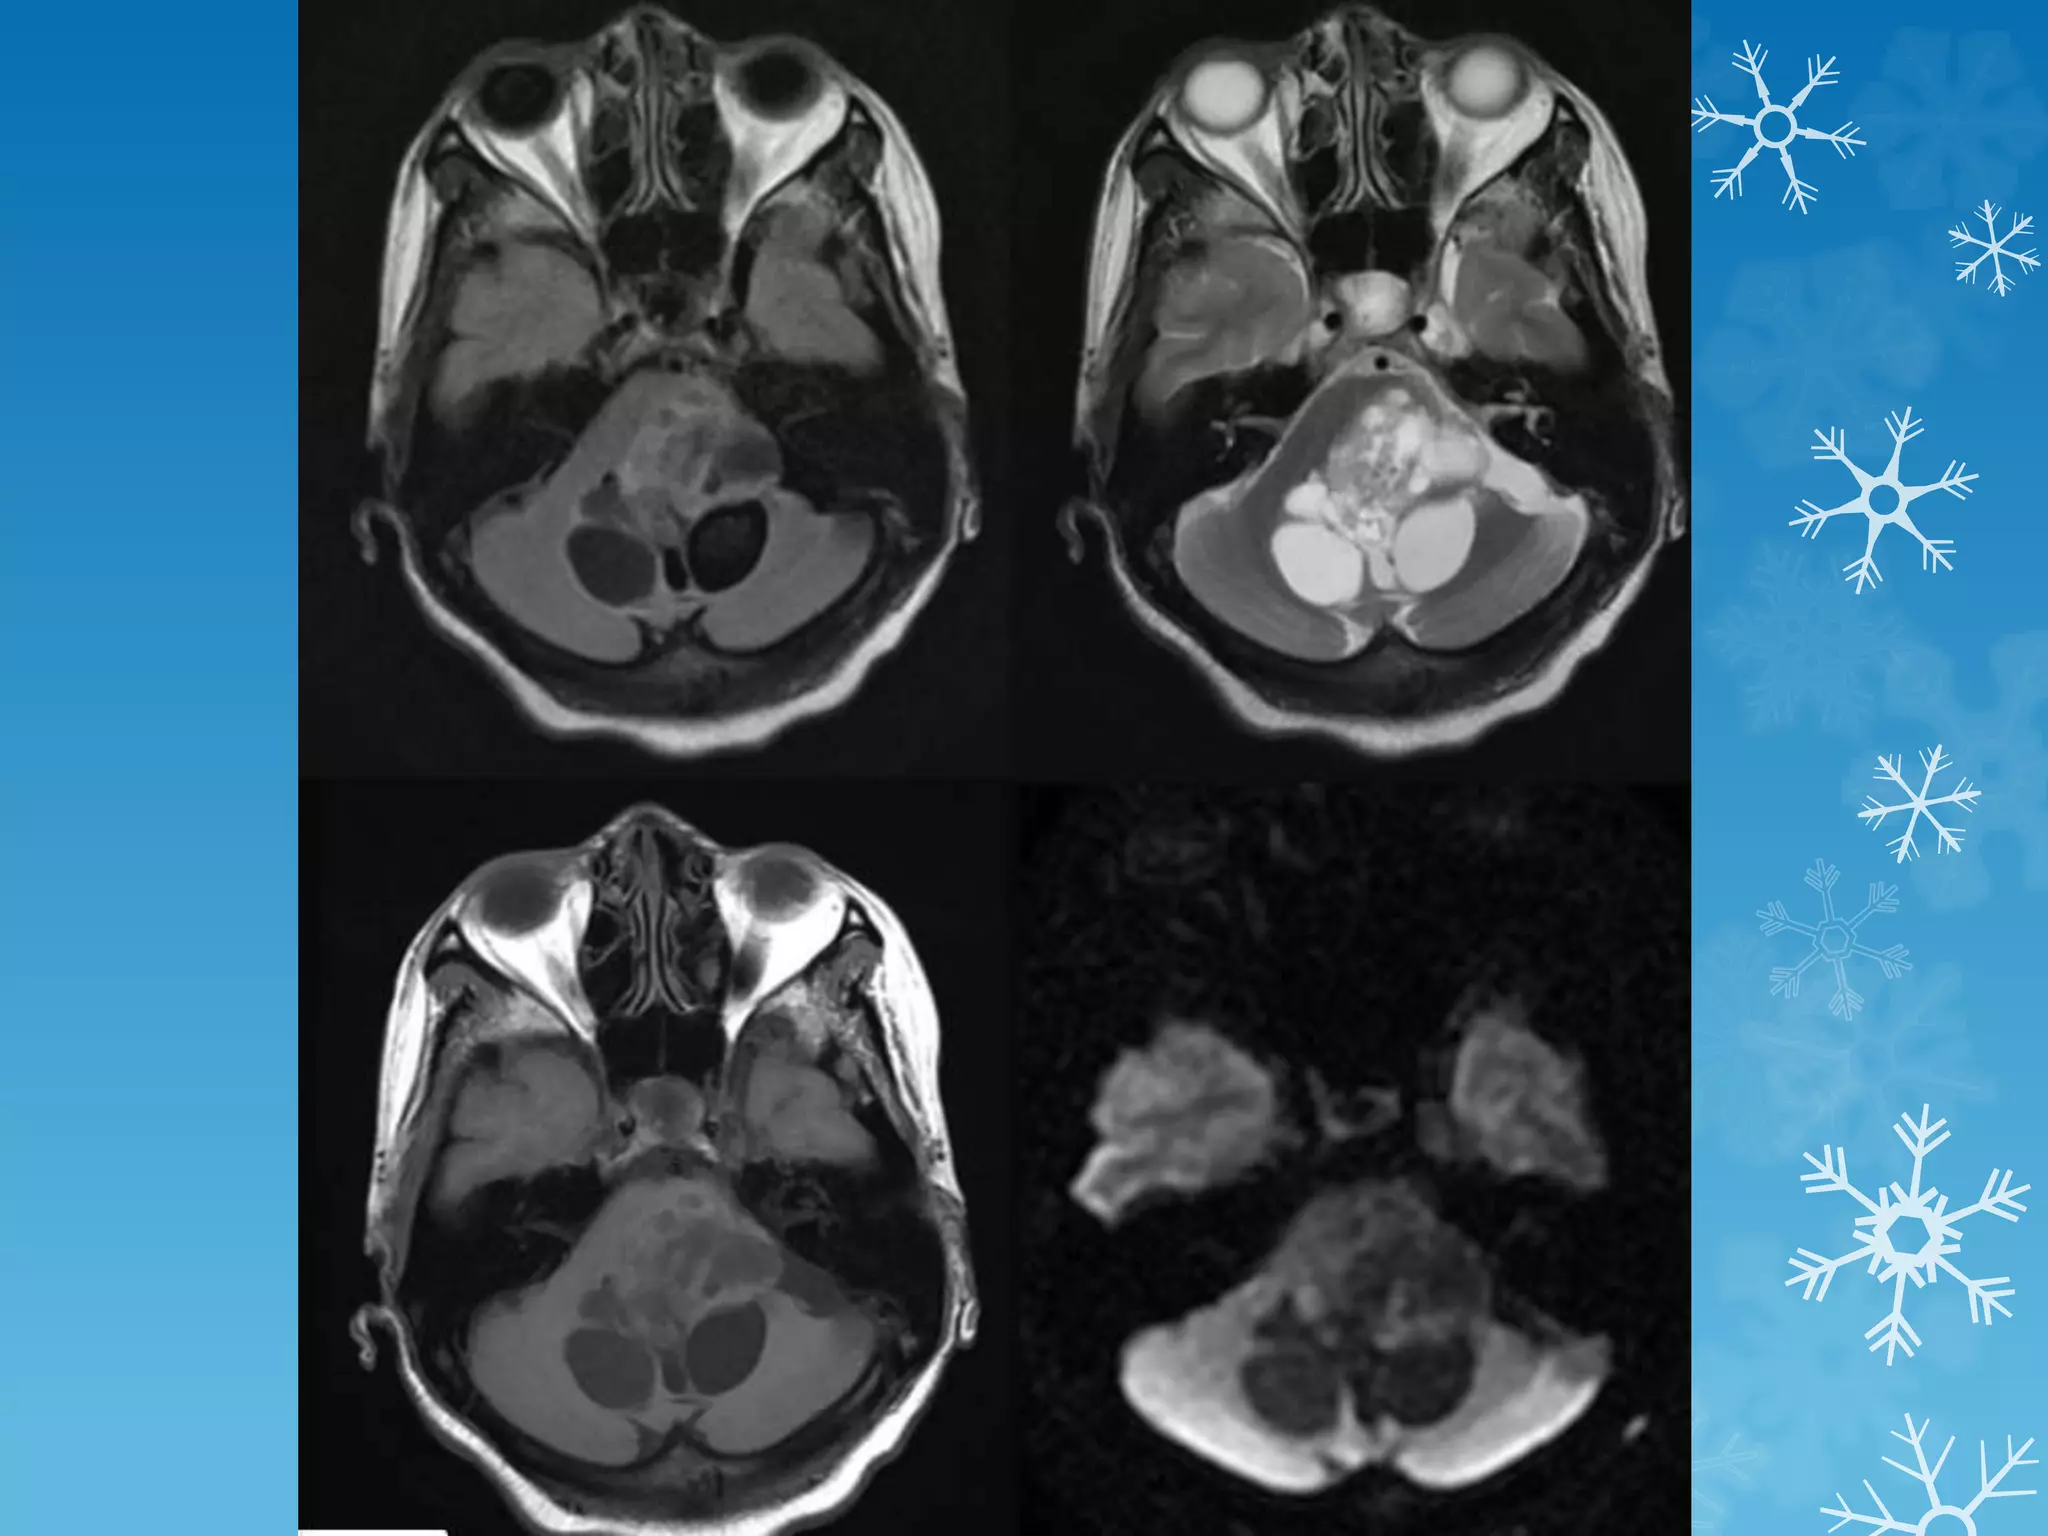

4th ventricle ependymoma

SPOT 5

CT MRI

Endolymphatic sac tumors (ELSTs)